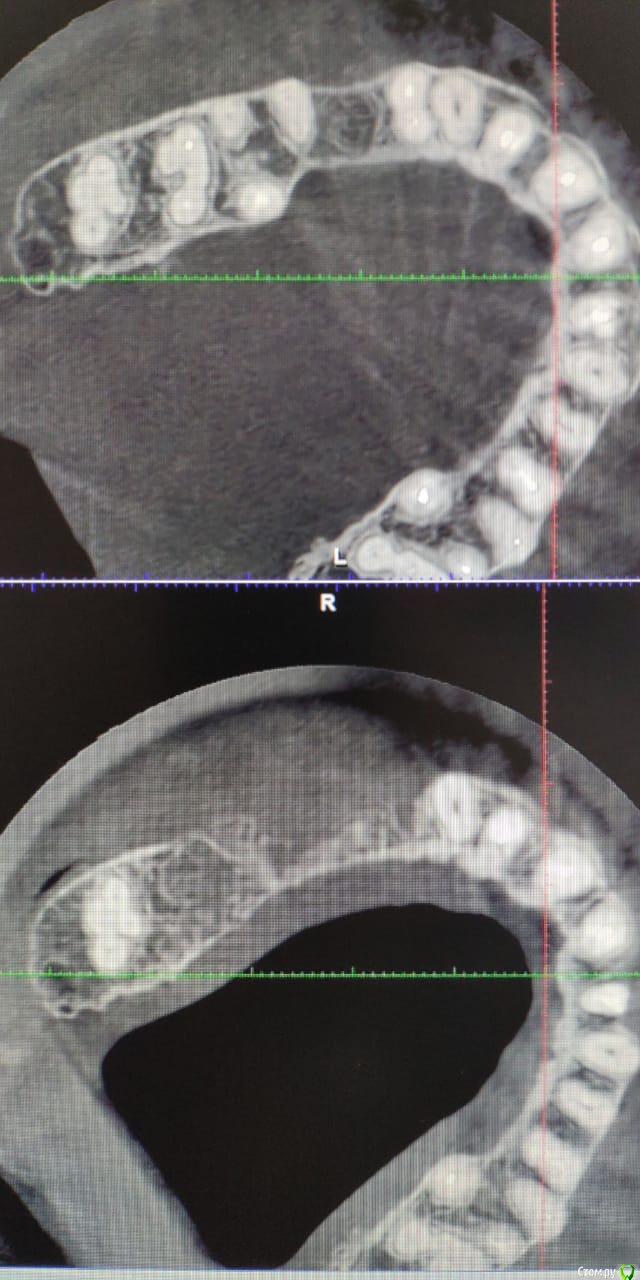

Irouil Опубликовано 14 октября, 2018 Поделиться Опубликовано 14 октября, 2018 Честно говоря, Ваши срезы с КТ не очень информативны, по ним сложно что-то подсказать Ссылка на комментарий

Лералена Опубликовано 14 октября, 2018 Автор Поделиться Опубликовано 14 октября, 2018 Честно говоря, Ваши срезы с КТ не очень информативны, по ним сложно что-то подсказать Я загружу немно позже ссылку на КТ, до имплантации, после и на сегодняшний день Ссылка на комментарий

Лералена Опубликовано 14 октября, 2018 Автор Поделиться Опубликовано 14 октября, 2018 https://cloud.mail.ru/public/2sk5/SAPv3y5D1 Это снимки КТ на сегодняшний день, прошло 3.5 месяца после удаления имплантатов и 7 зуба сверху рядом с ними. Ссылка на комментарий